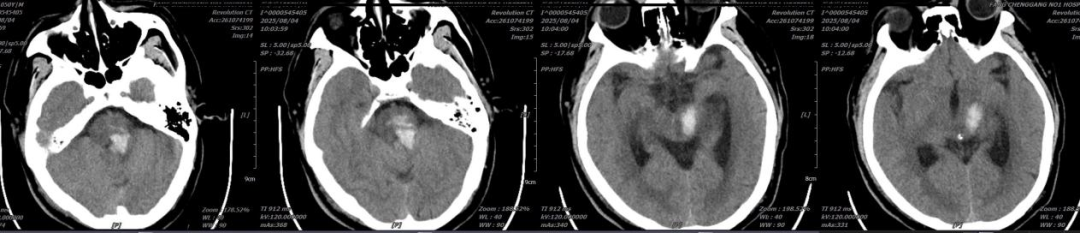

▲术前CT检查